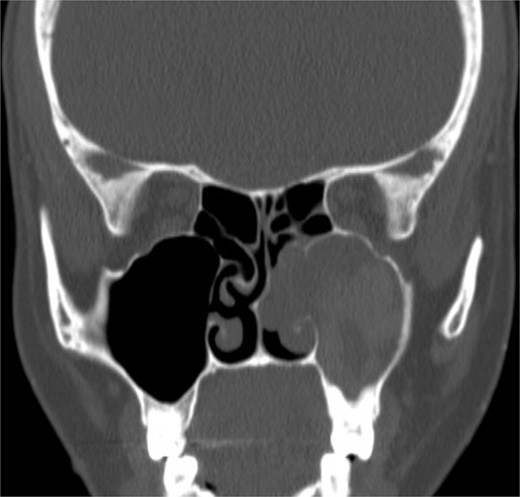

Coronal NCCT image of the paranasal sinuses showing isolated destructive right maxillary sinus lesion violating the right orbit.

An 18-year-old adolescent mentally challenged male was complaining of chronic right thick purulent nasal discharge, cough, and headache, which did not respond to multiple courses of oral antibiotics. Purulent discharge was seen filling the right nasal cavity and the nasopharynx during endoscopic examination. NCCT images (Fig. 7) revealed a destructive right maxillary sinus lesion. The patient underwent endoscopic sinus surgery, intra-operative frozen section showed granuloma, right medial maxillectomy with removal of the invasive fungal granuloma was performed (Fig. 8), and tissue cultures revealed Aspergillus flavus. Infectious disease team was involved, and the patient was started on a 6-months course of oral antifungal agent. The patient remained symptomless throughout his 1 year regular appointments.